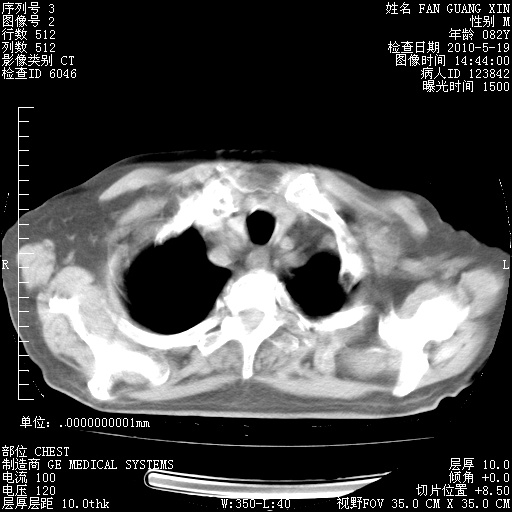

复查肺部CT,明显好转。为什么发热呢?

治疗3周后的肺部CT

治疗3周后的肺部CT纵隔窗